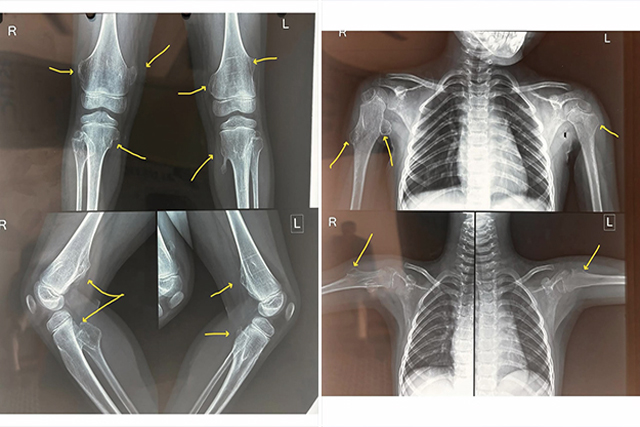

Multiple Hereditary Exostosis (MHE): Causes, Symptoms, and Treatment